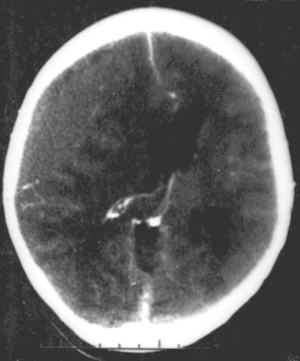

Nontraumatic epidural hematoma in a young woman. The grey area in the top left is organizing hematoma, causing midline shift and compression of the ventricle. | |

قد تبدي الصورة البسيطة للجمجمة وجود كسر. لكن الاختبار الأمثل للتشخيص هو التصوير الطبقي المحوري للدماغ CT.scan، فهو يُظهر النزف على شكل منطقة عالية الكثافة محدبة من الجهتين ومحاذية للجمجمة.